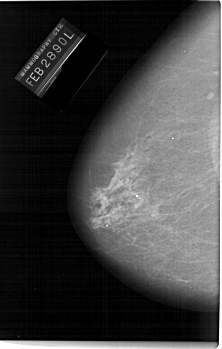

A_1144_1.RIGHT_CC

RIGHT_CC LINES 6676 PIXELS_PER_LINE 3526 BITS_PER_PIXEL 12 RESOLUTION 43.5 OVERLAY